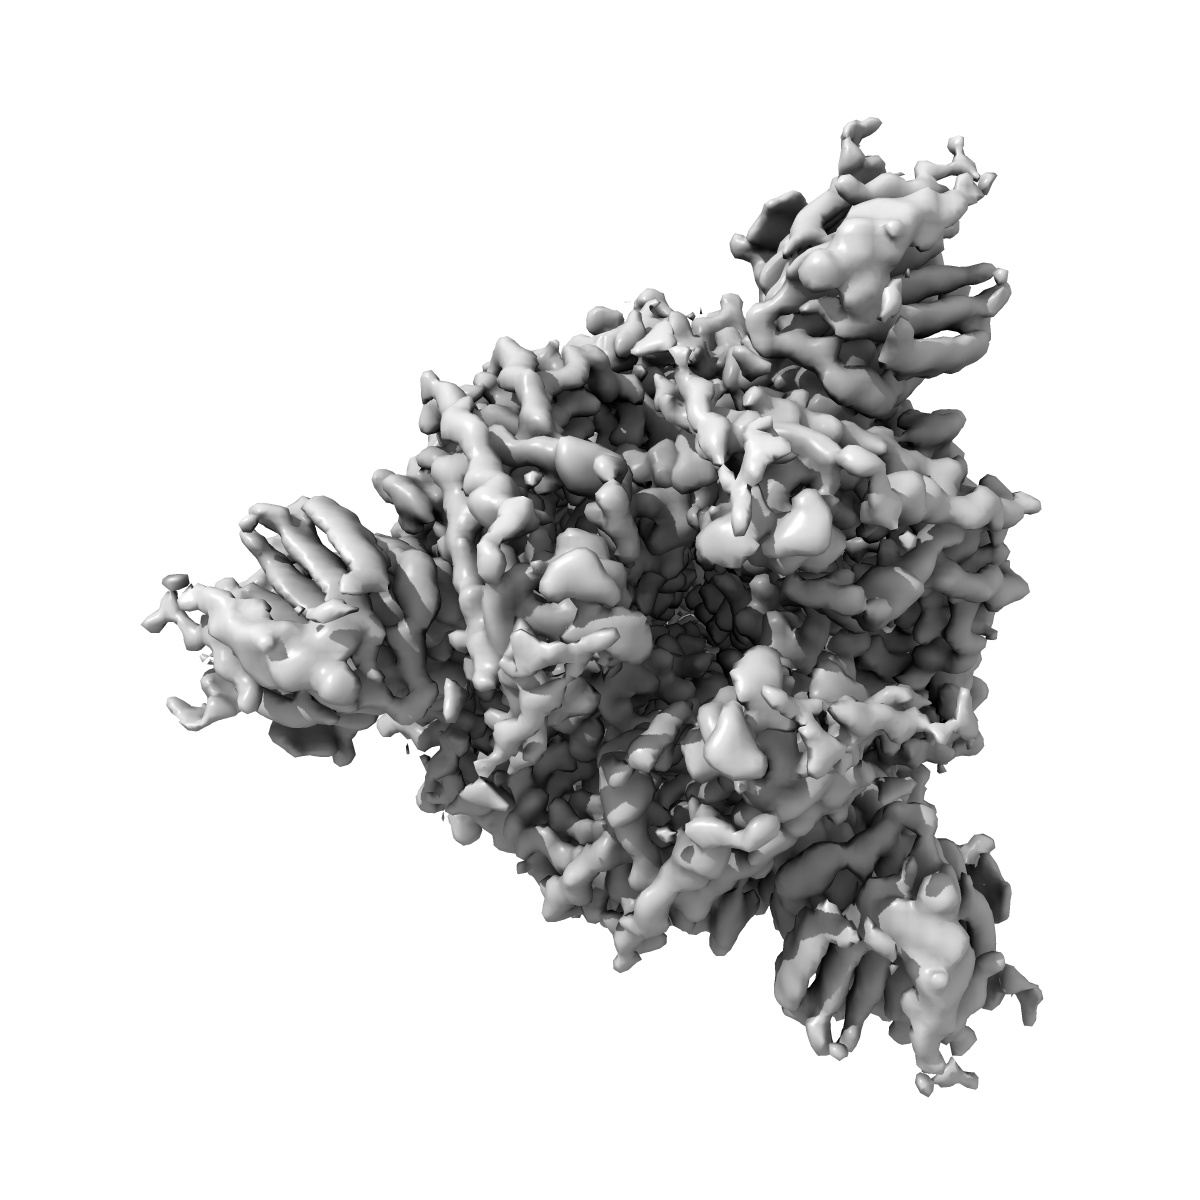

Cryo-EM structure of SARS-CoV-2 Spike Proteins on intact virions: B.1 variant 3 closed RBDs

Virion morphology and on-virus spike protein structures of diverse SARS-CoV-2 variants.

Ke Z , Peacock TP , Brown JC , Sheppard CM , Croll TI , Kotecha A , Goldhill DH , Barclay WS , Briggs JAG

(2024) EMBO J , 43 , 6469 - 6495